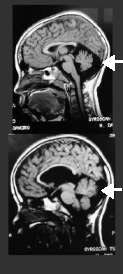

Macro Cisterna Magna

A Cisterna Magna

é um espaço na fossa posterior que recebe o líquido cerebrospinal

através do Foramen de Magendie. Embora seu alargamento tenha sido considerado

uma variante normal, hoje considera-se que está associado a distúrbios

do desenvolvimento cerebral, devido à sua associação

com problemas de neurodesenvolvimento.

Pode estar associada à alterações cerebelares, como

nos exemplos mostrados na figura. Como o Cerebelo

tem sido associado, também, a problemas de desenvolvimento cognitivo,

essa associação pode agravar a sintomatologia.